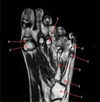

6

Q

What is letter D?

A

SUPRASPINATUS MUSCLE

How well did you know this?

1

Not at all

2

3

4

5

Perfectly

7

What is letter A?

SUBSCAPULARIS MUSCLE

BASE OF 2ND METACARPAL

74

What is letter B?

TRAPEZOID

75

What is letter C?

CAPITATE

76

SCAPHOID

77

What is letter E?

RADIUS

78

What is letter F?

ULNA

79

What is letter K?

LUNATE

80

What is letter G?

TRIQUETRIUM

81

What is letter H?

HAMATE

82

What is letter J?

BASE OF 5TH METACARPAL

IP JOINT

84

MCP JOINT

85

HEAD OF METACARPAL

86

What is letter D

87

TRIQUETRUM

88

89

90

HEAD OF 2ND PROXIMAL PHALANX

91

92

BASE OF 2ND MIDDLE PHALANX